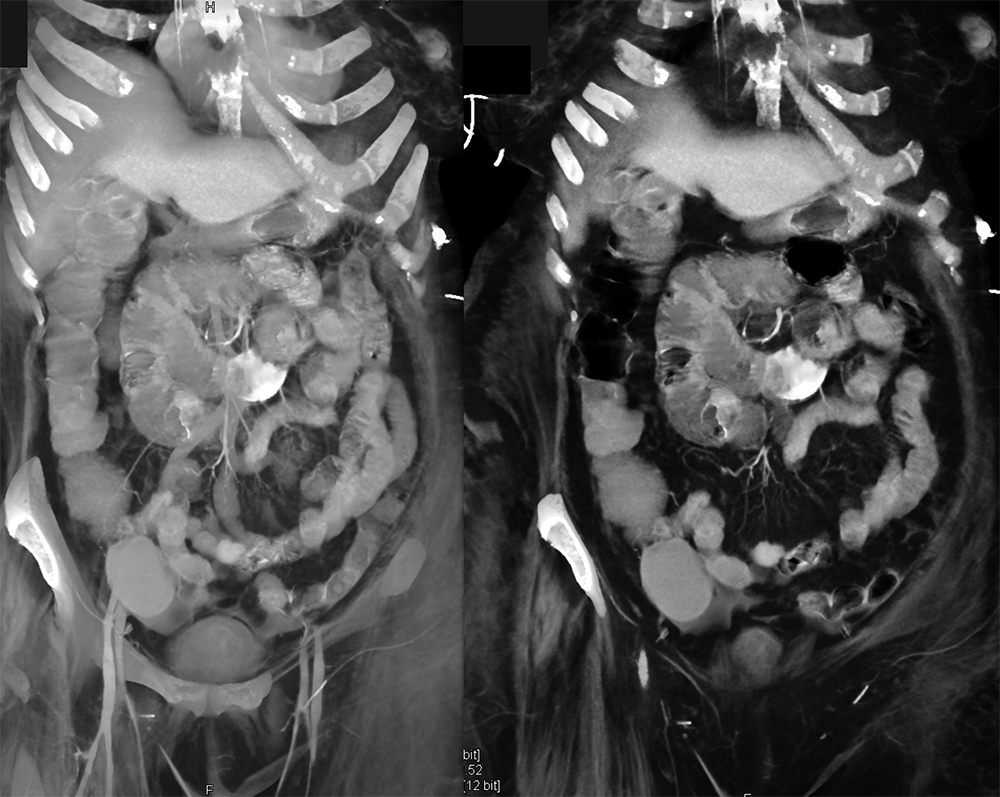

GIST Tumor Jejunum as the Cause of GI Bleeding ![]() |

![]() |

GI Bleed ![]() |